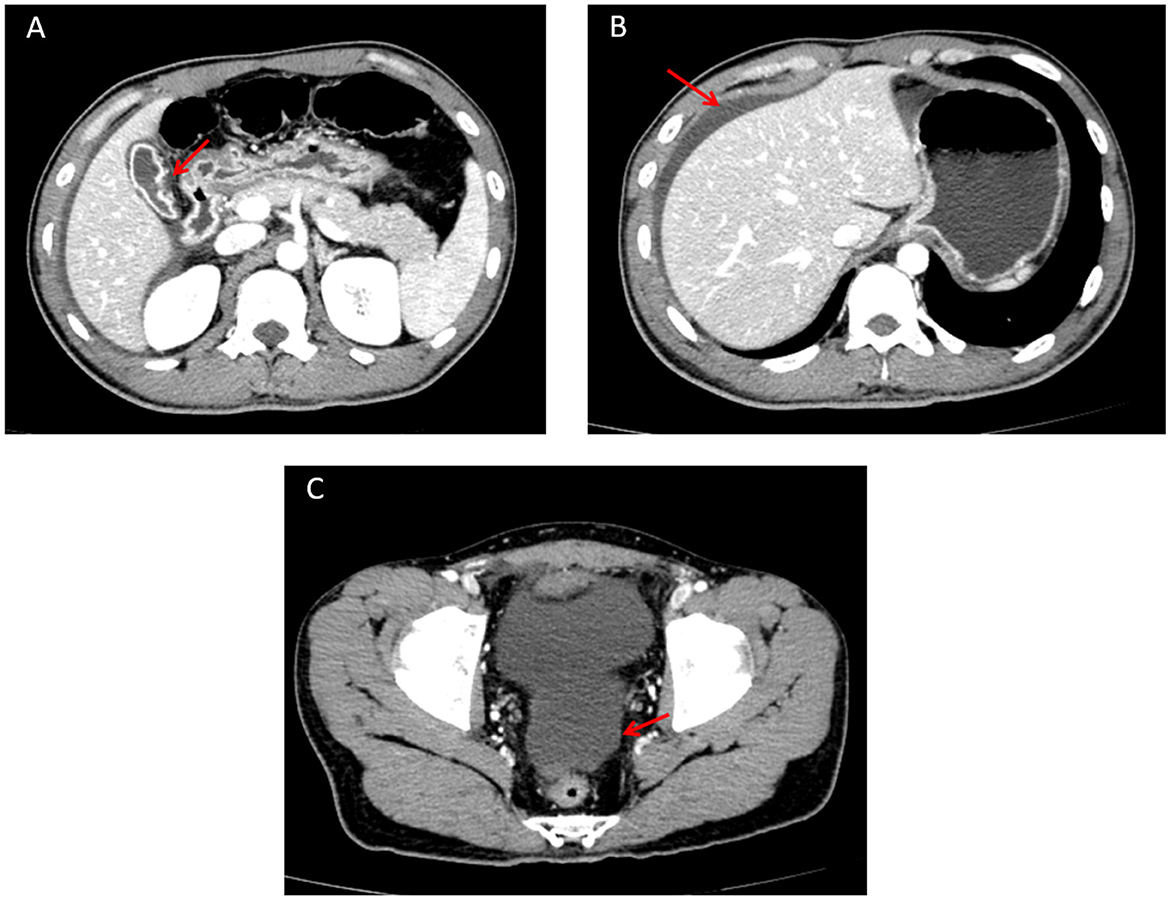

Concurrently, an urgent contrast-enhanced abdominal CT scan was performed, and the radiology department issued a critical value report as follows: the gallbladder is not enlarged but has a thickened wall with interrupted continuity and indistinct margins adjacent to the duodenum; no gallstones are seen in the lumen (Figure 1A). The liver has a smooth outer margin, normal morphology, size, and hepatic lobe proportions. No intrahepatic or extrahepatic bile duct dilatation is observed, and the hepatic hilum shows a clear structure without abnormal density (Figure 1B). Additionally, a pelvic fluid collection is noted on abdominal computed tomography (Figure 1C). After fully informing the patient and family, surgical exploration was immediately initiated.

Figure 1. Abdominal contrast-enhanced CT image. (A) Perforated gallbladder (showing interrupted continuity and indistinct margins of the gallbladder wall adjacent to the duodenum) on abdominal computed tomography. (B) Perihepatic fluid collection, with the liver demonstrating a smooth outer margin, normal morphology, size, and hepatic lobe proportions, on abdominal computed tomography. (C) Pelvic fluid collection on abdominal computed tomography.